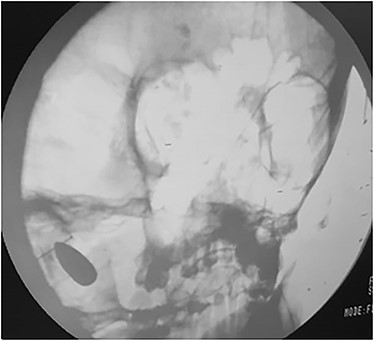

A plain skull X-ray was obtained and it revealed that the bullet had inversed and migrated upwards inside the left cerebellar hemisphere (Fig. 3).

Intra-operation skull X-ray revealed that bullet had inversed and migrated upwards inside the left cerebellar hemisphere.

Another maneuver was done and the bullet was removed.